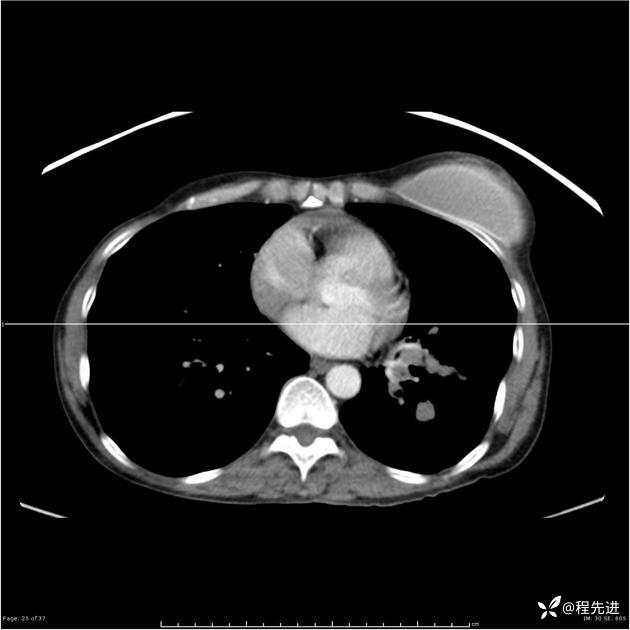

病例女,53岁,气管、左主支气管、下叶支气管内结节,乳头状瘤?期待你的精彩解读

女,53岁

乳头状瘤?